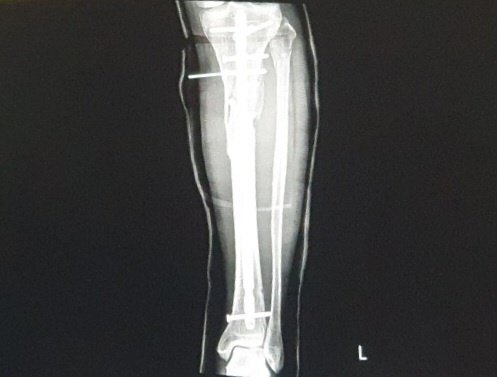

경골 플레이트 수술 결과

다리를 절개하여 부러진 정강이뼈에 금속판을 대고

긴 못으로 고정하고 나사를 조이는 수술이다.

3시간의 기나긴 수술이 진행되고, 내 다리 속에는 철심이라는 물체가 삽입되었다.

무릎 바로 아래가 골절. 파쇄되어 어려운 수술이었단다.